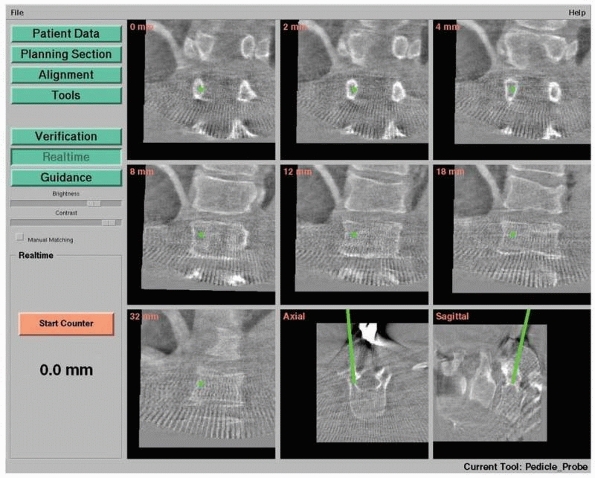

CT images during surgery when necessary.9,12 Figure 17-8 shows an example of navigation with 3D fluoroscopy.

FIGURE 17-8

Pedicle screw insertion with three-dimensional fluoroscopy. Screen view of three-dimensional fluoroscopy navigation during pedicle screw insertion in a fractured thoracic vertebra with the SireMobil Iso-C 3D (Siemens Medical Solutions, Erlangen, Germany). (Image courtesy of Prof. F. Gebhard.) |